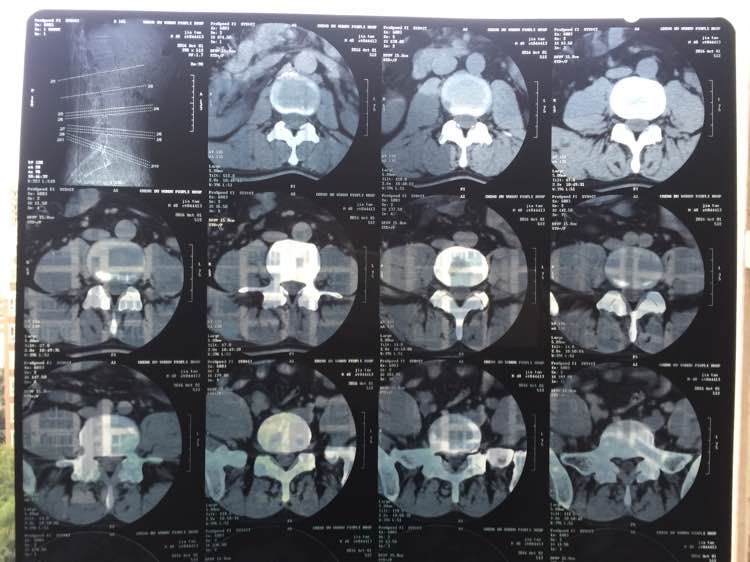

酸痛感,不是那种钻心痛的感觉,坐下时很难受,持续2个月了,几乎是突然发生的,以前从来没这样过。到医院检查拍片,医生说是腰椎间盘突出,但不严重。给我开了云南白药气雾剂喷剂和一盒化淤的药。喷了几天有改善,但过了几天有了抗药性就没用了。每天稍微坐久就酸痛,很痛苦。该怎么办啊,求指点。